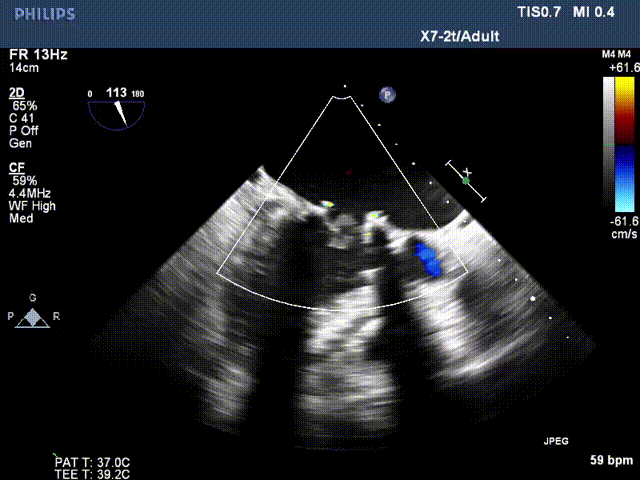

术前超声:

长轴切面二尖瓣狭窄伴关闭不全